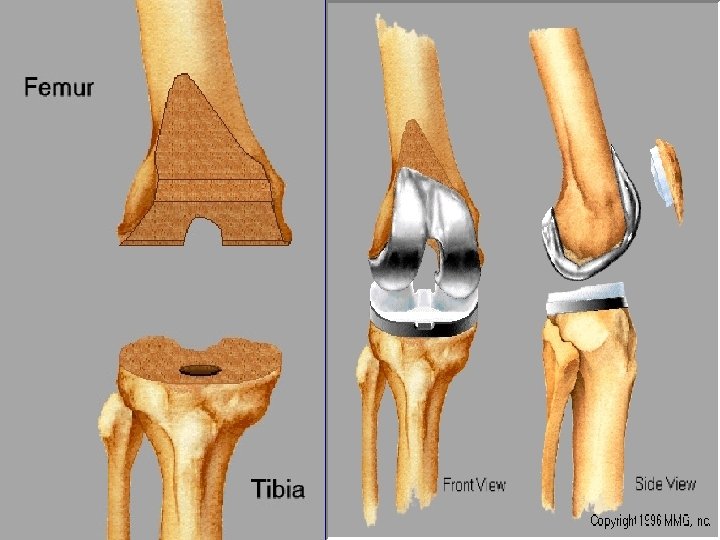

componenten

Knieprothese